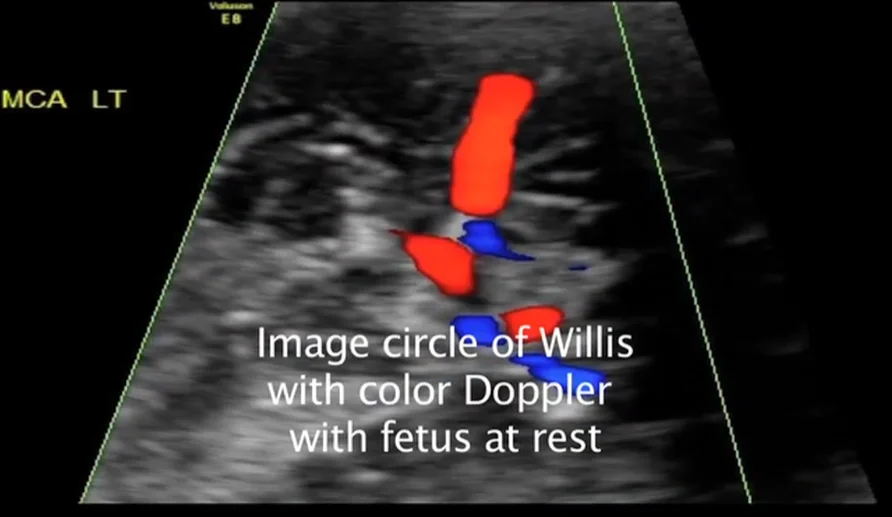

• Doppler trong sản khoa

• Thiếu máu thai nhi (Fetal Anemia)